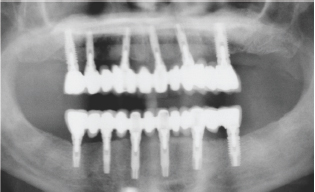

Some cases of period on it is in diabetics are diagnosed very late. At this time, teeth have lost most of their support and must be extracted. Fortunately we can use nowadays predictable techniques to regenerate bone for placing dental implant to achieve a new dentition (Figure 4-6) [5,6].

Figure 6: Patient 2: Panoramic X ray with implants supporting a fix upper and lower prosthesis.